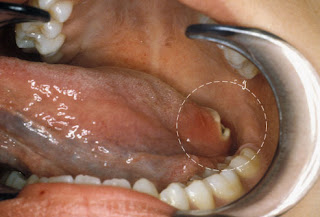

face cancer